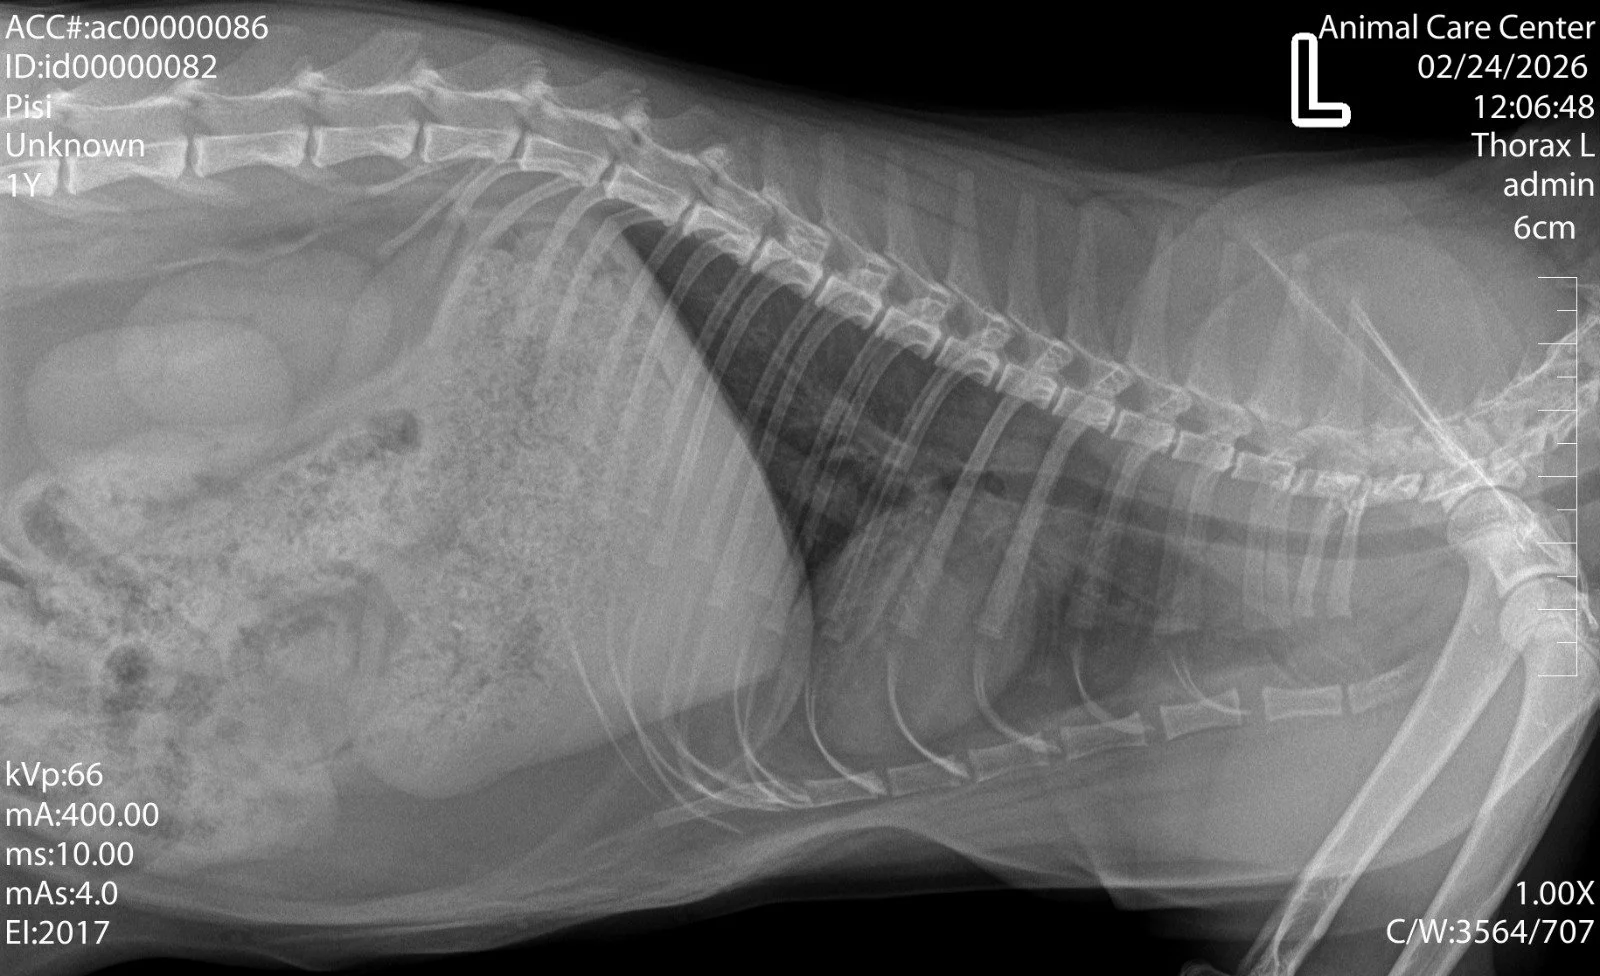

Radiografie veterinară: ce este, când se recomandă și de ce este esențială pentru un diagnostic corect

Radiologia este o parte esențială a medicinei veterinare moderne. Fie că este vorba despre un accident, o problemă digestivă, o durere apărută brusc sau o suspiciune de boală internă, radiografia ajută medicul să obțină rapid informații importante despre starea de sănătate a animăluțului tău.